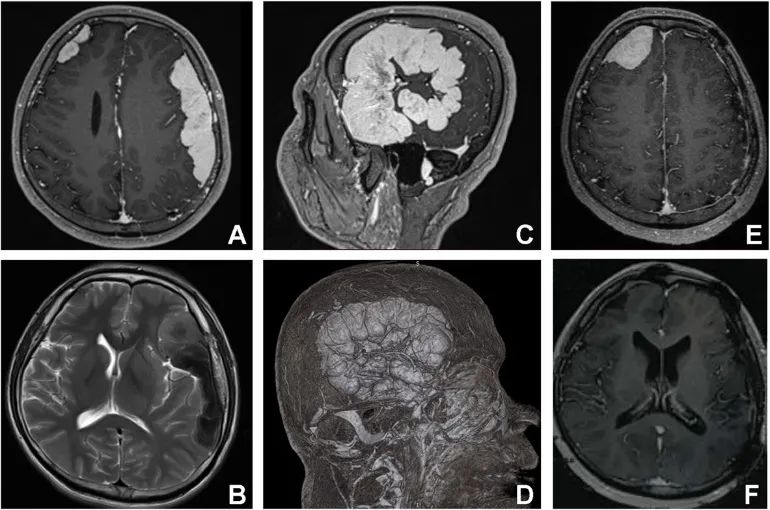

磁共振成像(MRI)检测到两个轴外、均匀、边界清晰的硬脑膜病变。大的在左额颞顶叶区,小的在右额区。T1加权图像显示等信号和稍高信号,T2加权图像显示等信号和病灶内低信号病灶,明显均匀增强,伴有增强的硬脑膜尾征(图1)。

▲ 图1